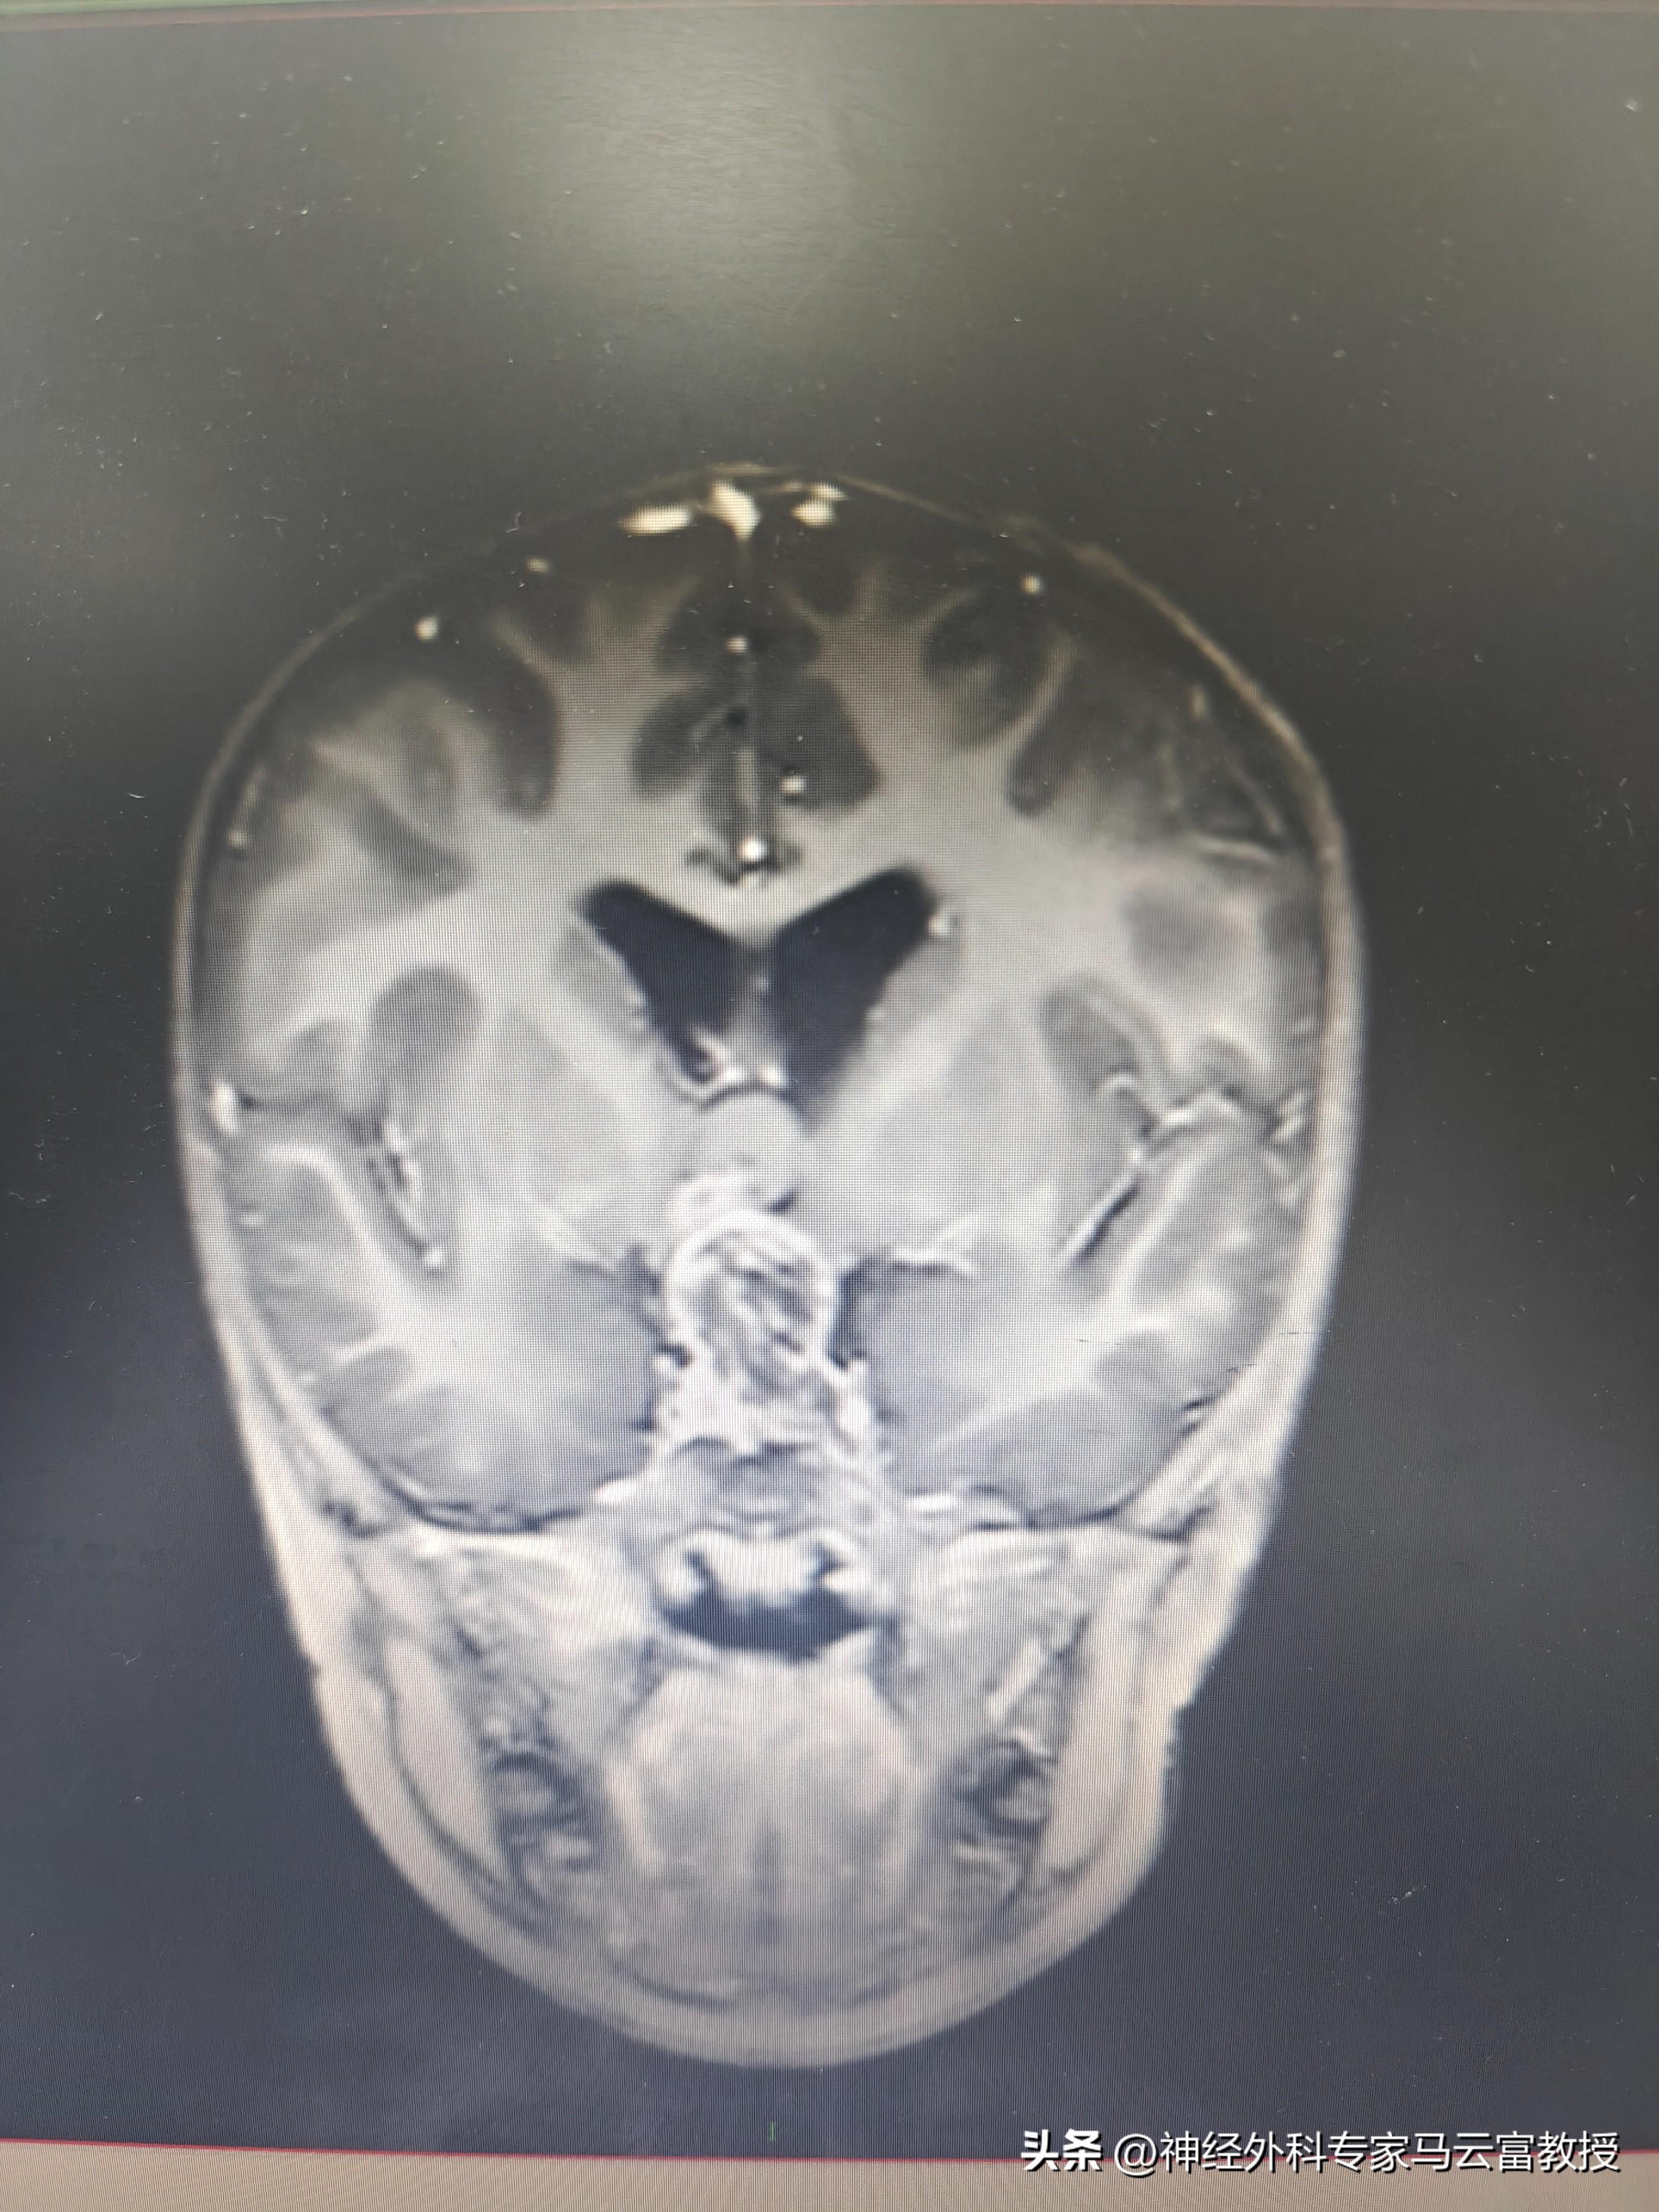

顱內佔位CT